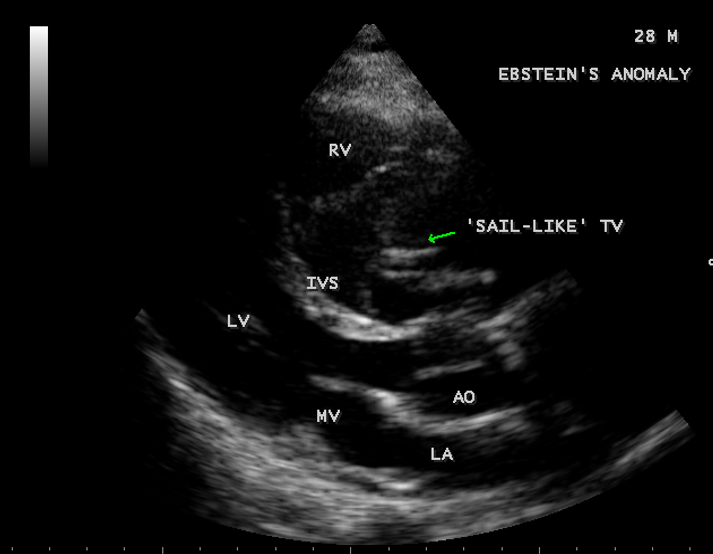

A 28-year old male presented with cyanosis and auscultation revealed a ‘sail sound’ ( loud tricuspid component of first heart sound due to increased tension developed by the large anterior leaflet as it reaches the limits of its systolic excursion- an important sign of anterior leaflet mobility), a ‘cadence’ quality of quadruple rhythm due to wide splitting of first and second sounds ( due to complete right bundle branch block), atrial and ventricular filling sounds (summation of these sounds due to prolonged PR interval). ECG revealed the features of Ebstein’s anomaly as shown in Figures 11 and 12. X-ray chest revealed the Ebstein’s configuration as shown in Figure 13. 2D echocardiography revealed a ‘sail-like’anterior tricuspid leaflet forming a ‘muscular curtain’ in between the inflow and trabecular parts of the right ventricle as an ‘imperforate membrane’ with a ‘pinhole’communication, associated with a muscular VSD (ventricular septal defect) in the proximal, atrialized compartment of right ventricle suggesting an ‘atretic” (‘imperforate’) Ebstein’s anomaly as shown in Figures 14 to 27.

The anterior tricuspid leaflet is not involved in the process of downward displacement, it may be abnormally inserted occasionally and Shiina, et al documented the apical displacement of anterior tricuspid leaflet in 14% of cases echocardiographically [39]. The anterior leaflet forms a large, sail-like intracavitary curtain as in Figures 14, 25 and contains muscular strands instead of consisting entirely of a fibrous membrane as in the normal tricuspid valve [40]. It is potentially mobile with a brisk sail-like movement as shown in Figure 21 to 24 [41], free bloating with a ‘whipping motion’ across the right ventricular outflow tract (RVOT) as shown in Figure 26 and in some cases, the movement is restricted due to its adherence to the ventricular wall as in Figure 1 and 2, 4 and 9. It is often fenestrated, may in part be musculaized , inserting into the trabeculations of the right ventricle (RV) as in Figure 28 and rarely, the anterior leaflet forms an ‘atretic’ membrane that spans the midportion of the right ventricular cavity as in Figure 16.

Valvuloplasty It is favoured if the anterior leaflet is suitable for use as a functional monocuspid valve. The leaflet must exhibit adequate excursion and be free of large fenestrations. If the leaflet is ‘sail-like’ and free and when the tricuspid annulus is markedly dilated, an aggressive “Kay annuloplasty” is preferred as for case 4.